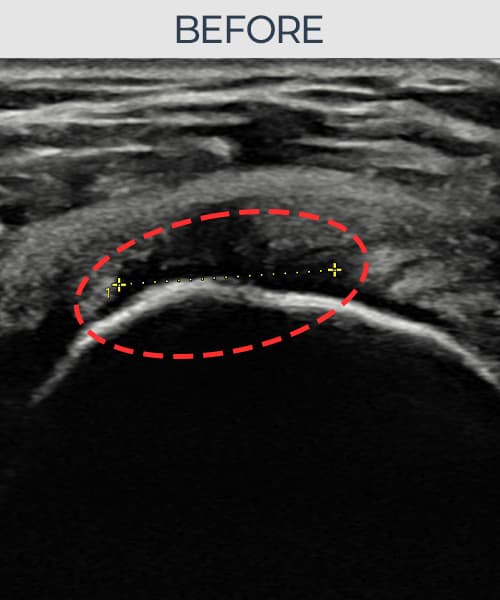

[経過期間: 23.07.18~23.09.14]

[縫縮術] 超音波検査にて左 棘上筋腱 광범위 部分断裂(15mm × 6mm (腱厚の約70%欠損))を確認。縫縮術施行後、腱の連続性が回復し、日常生活に復帰されました。